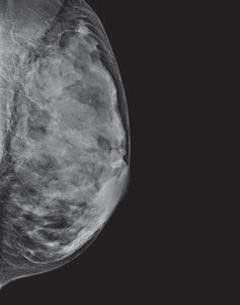

Categorías de densidad de los senos

Los radiólogos utilizan el sistema BI-RADS para clasificar la densidad mamaria en 4 categorías que van desde tejido adiposo casi en su totalidad hasta tejido extremadamente denso con muy poca grasa:

Algunos informes de mamografía que se envían a las mujeres indican la densidad mamaria. Su médico también puede decirle si su mamograma muestra que usted tiene senos densos.

¿Por qué es importante la densidad de los senos?

Las mujeres con tejido mamario denso parecen tener un riesgo ligeramente mayor de padecer cáncer de seno que las mujeres con tejido mamario menos denso. Por el momento, no está claro por qué el tejido mamario denso está relacionado con el riesgo de padecer cáncer de seno.

Sabemos que el tejido mamario denso dificulta que los radiólogos detecten el cáncer. En los mamogramas, el tejido mamario denso se ve blanco. Las masas o tumores de los senos también lucen de color blanco, por lo que la densidad del tejido puede ocultar algunos tumores. Por el contrario, tejido graso se ve casi negro. Sobre un fondo negro es más fácil identificar un tumor que se ve blanco. Por esta razón, los mamogramas pueden ser menos precisos en mujeres con senos densos.